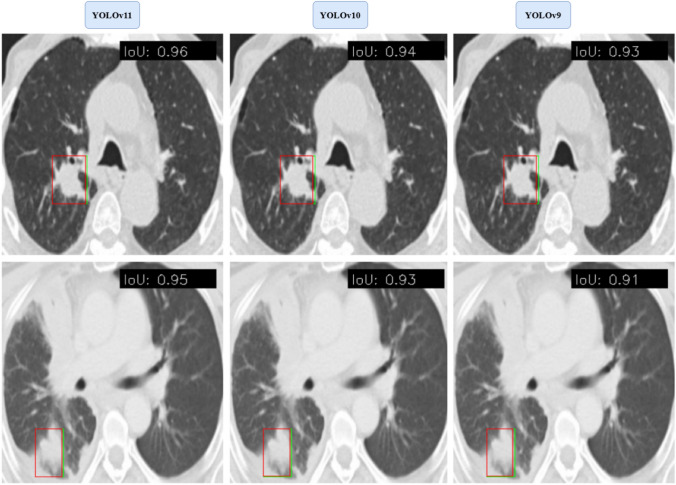

Figure 8 illustrates the YOLOv11 model's performance in lung tumor localization by comparing the predicted bounding boxes (Red) with the ground truth annotations (Green). The visualization demonstrates a significant overlap between the predicted and actual tumor regions, highlighting the model's precision in identifying and localizing tumors within CT scans. This comparison further validates the model's effectiveness in handling complex tumor morphologies and varying imaging conditions. The results demonstrate the superior performance of YOLOv11 in detecting and localizing lung tumors. The following section discusses these findings in the context of existing research, highlighting the strengths and limitations of our approach and its implications for clinical applications.

Fig. 8.

Accurate localization of lung tumors: predicted (red) vs. ground truth (green) bounding boxes